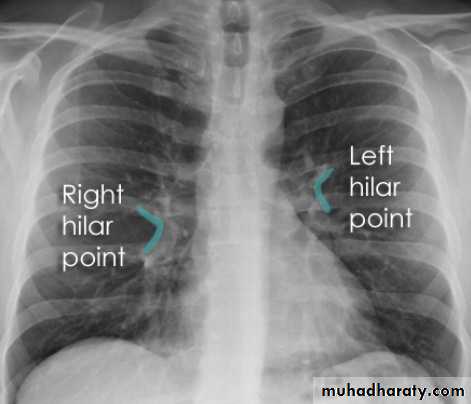

Hilar structuresThe hila (lung roots) are complicated structures mainly consisting of the major bronchi and the pulmonary veins and arteries. These structures pass through the narrow hila on each side and then branch as they widen out into the lungs. The hila are not symmetrical but contain the same basic structures on each side.

Each hilum contains major bronchi and pulmonary vessels

There are also lymph nodes on each side(not visible unless abnormal)

The left hilum is often higher than the right

Both hila should be of similar size and density. If either hilum is bigger and more dense, this is a good indication that there is an abnormality.